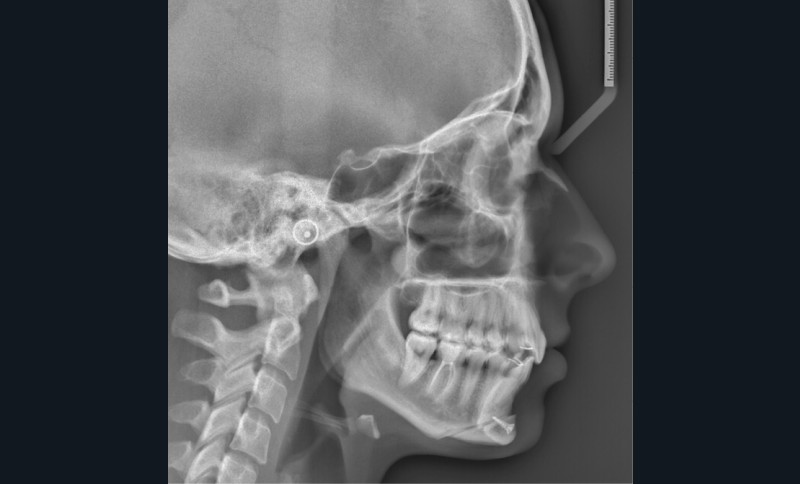

Examens complémentaires (fig. 3a,b)

À la radiographie panoramique, 31 présente une importante image apicale, confirmée par une radiographie rétroalvéolaire et également visible sur la téléradiographie de profil.

Cette dernière montre un schéma squelettique de Classe I et une typologie verticale normodivergente. Les rapports incisifs sont normaux et l’épaisseur des tissus mentonniers est insuffisante pour obtenir la fermeture buccale sans contraction. La symphyse est fine et l’incisive est centrée sur celle-ci.